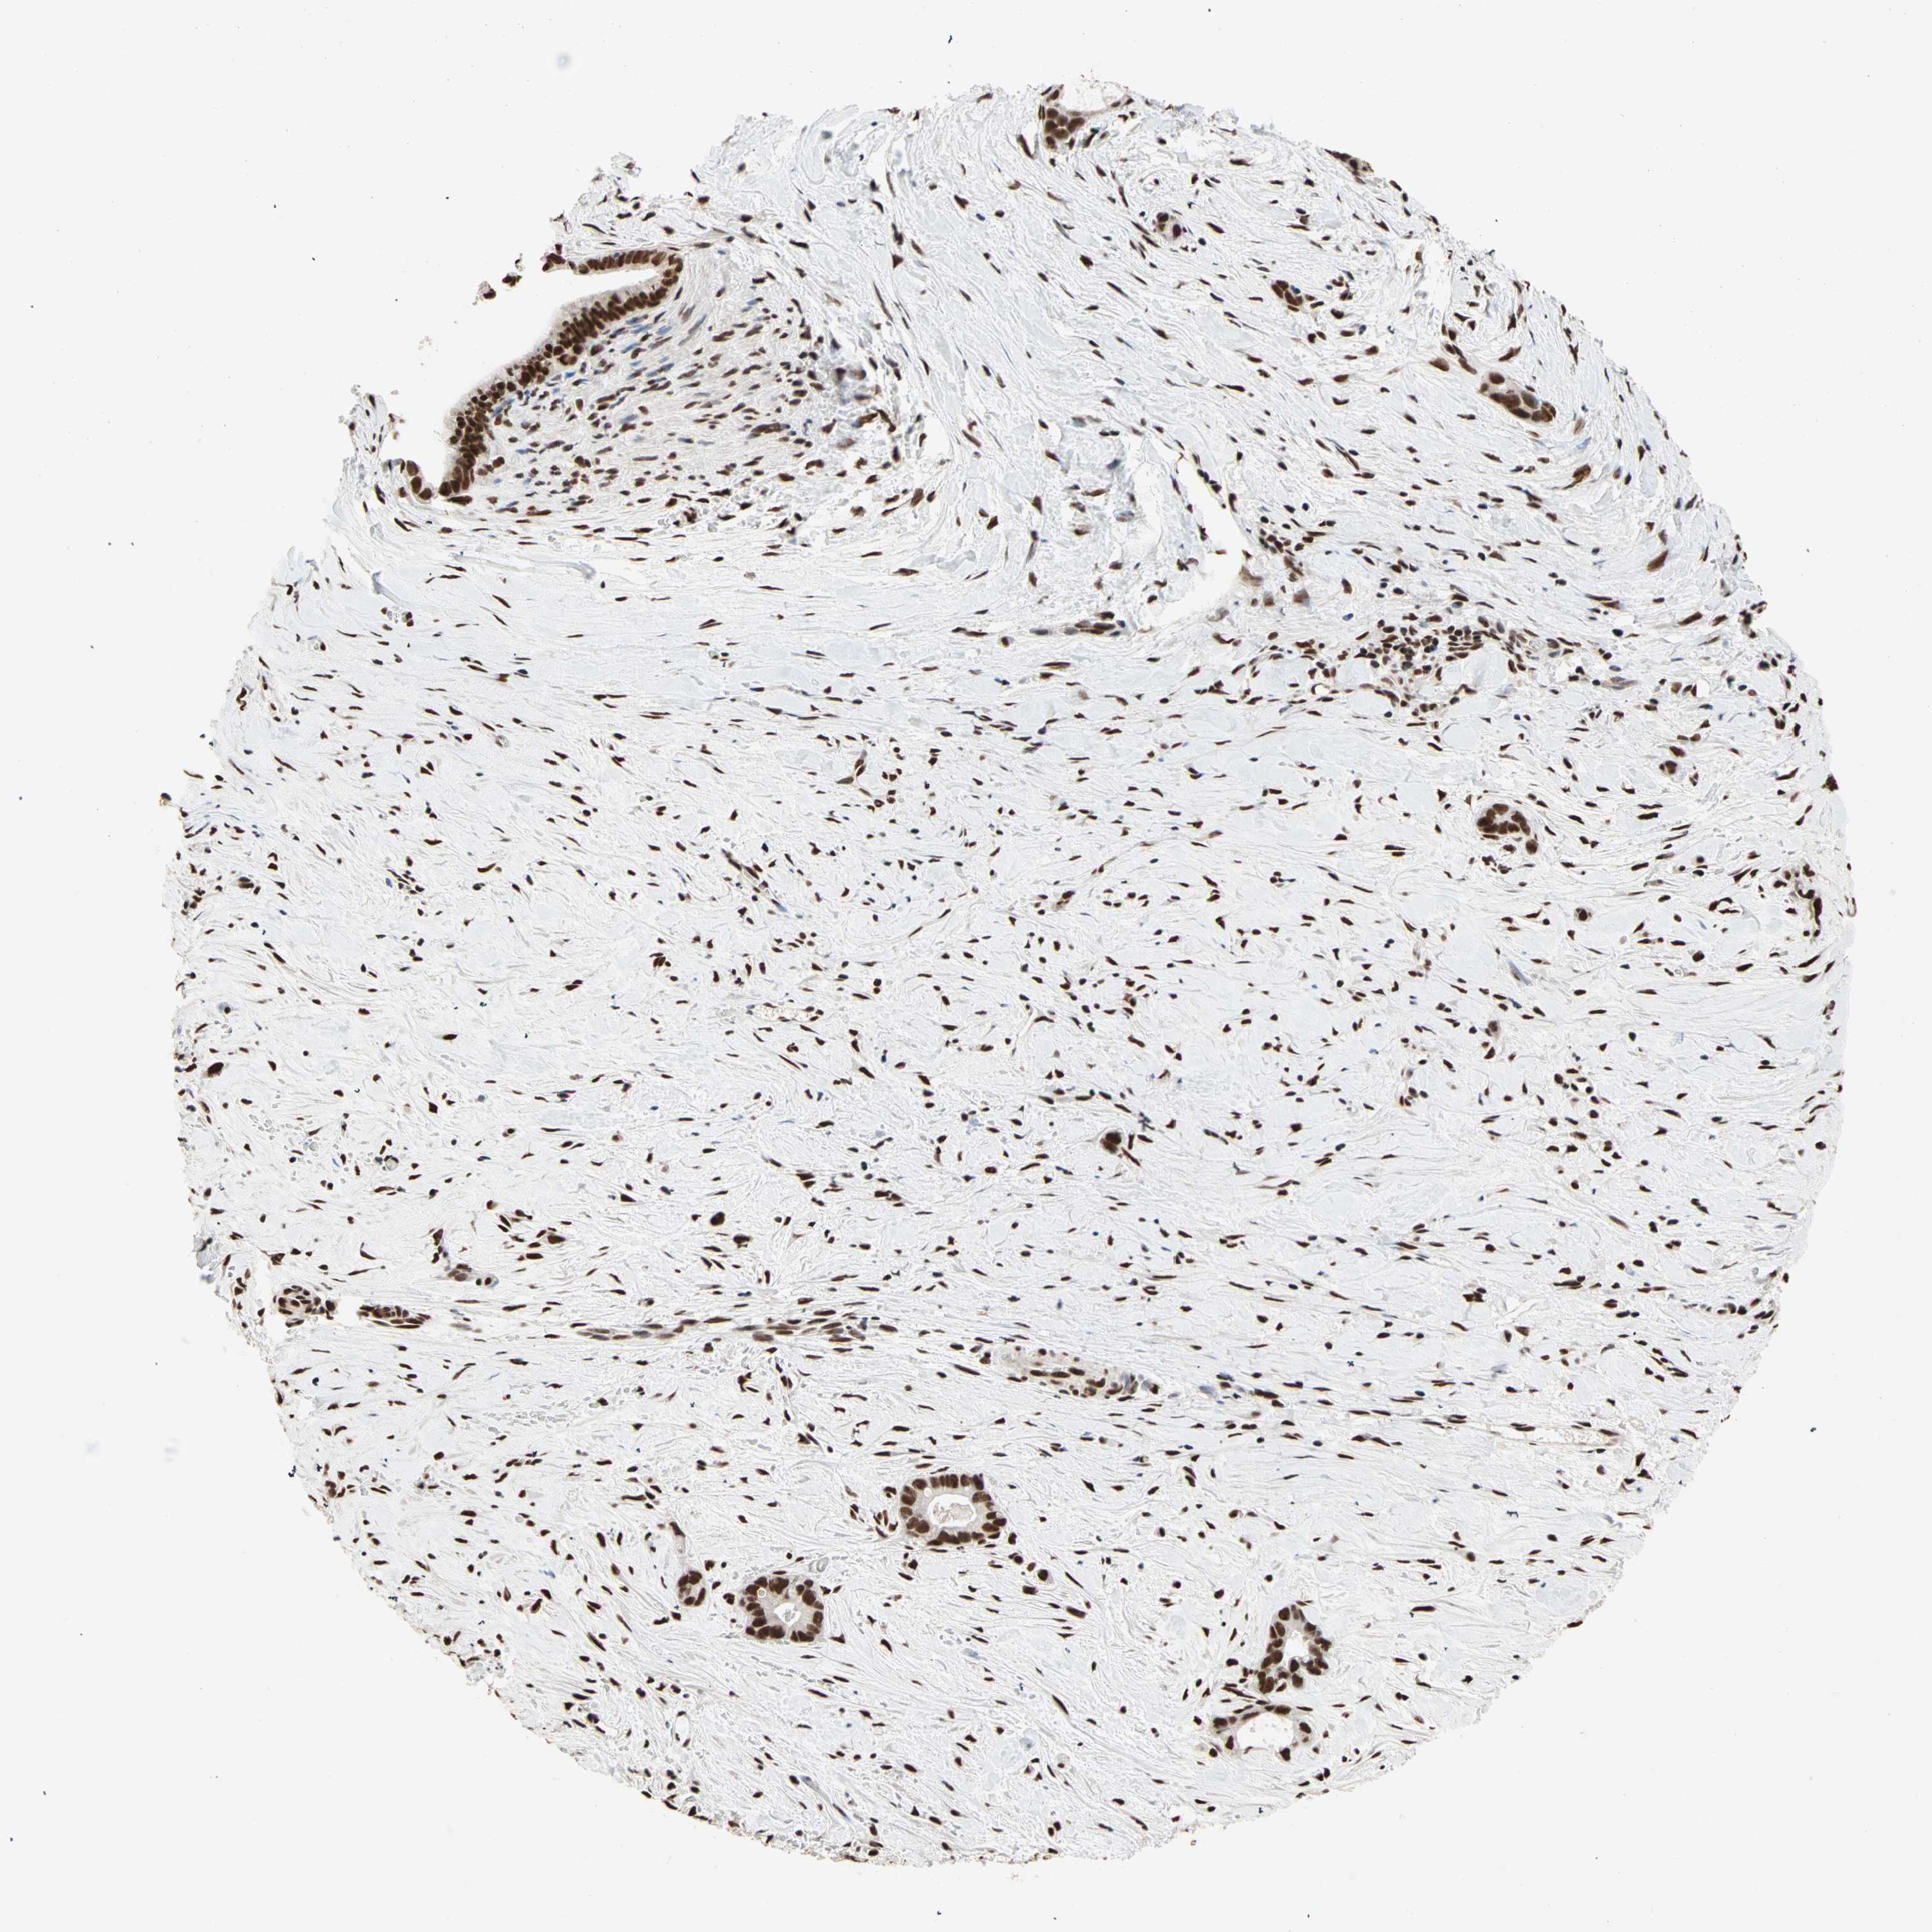

LIVER CANCER - Protein expressioni

A mouse-over function shows sample information and annotation data. Click on an image to view it in a full screen mode. Samples can be filtered based on level of antibody staining by selecting one or several of the following categories: high, medium, low and not detected. The assay and annotation is described here.

Note that samples used for immunohistochemistry by the Human Protein Atlas do not correspond to samples in the TCGA dataset.

Antibody stainingi

Antibody staining in the annotated cell types in the current human tissue is reported as not detected, low, medium, or high, based on conventional immunohistochemistry profiling in selected tissues. This score is based on the combination of the staining intensity and fraction of stained cells.

Each image is clickable and will lead to virtual microscopy that enables deeper exploration of all samples and also displays staining intensity scores, fraction scores and subcellular localization as well as patient and tissue information for each sample.

Antibody HPA007484

Staining

High

Medium

Low

Not detected

Intensity

Strong

Moderate

Weak

Negative

Quantity

>75%

75%-25%

<25%

None

Location

Nuclear

Cytoplasmic/membranous

Cytoplasmic/membranous,nuclear

Cholangiocarcinoma

Carcinoma, Hepatocellular, NOS